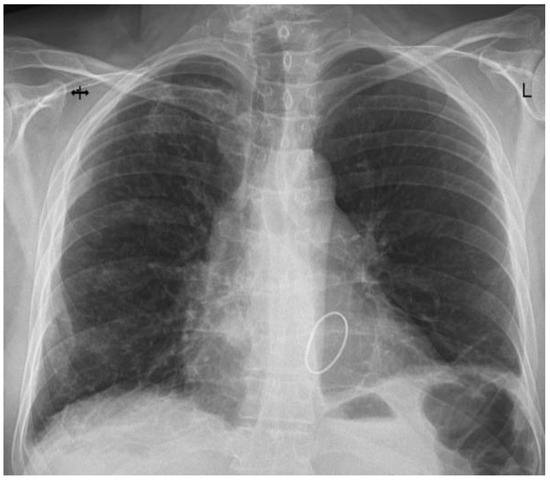

| Preoperative findings | The patient was referred for progressively worsening dyspnea and fatigue and diagnosed with severe mitral regurgitation. Transthoracic echocardiography revealed severe mitral regurgitations caused by posterior leaflet prolapse and flail due to chordae rupture. | |

| Postoperative evolution | Right after Intensive Care Unit (ICU) admission, hypoxia abruptly developed, and serous discharge was aspirated through the endotracheal tube. The thoracic X-ray performed revealed dense alveolar opacities on the entire right hemithorax, confirming the diagnosis of unilateral pulmonary edema. | |